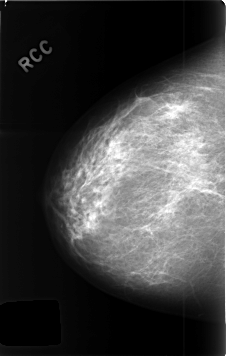

C_0435_1.RIGHT_CC

RIGHT_CC LINES 4616 PIXELS_PER_LINE 2936 BITS_PER_PIXEL 12 RESOLUTION 50 NON_OVERLAY